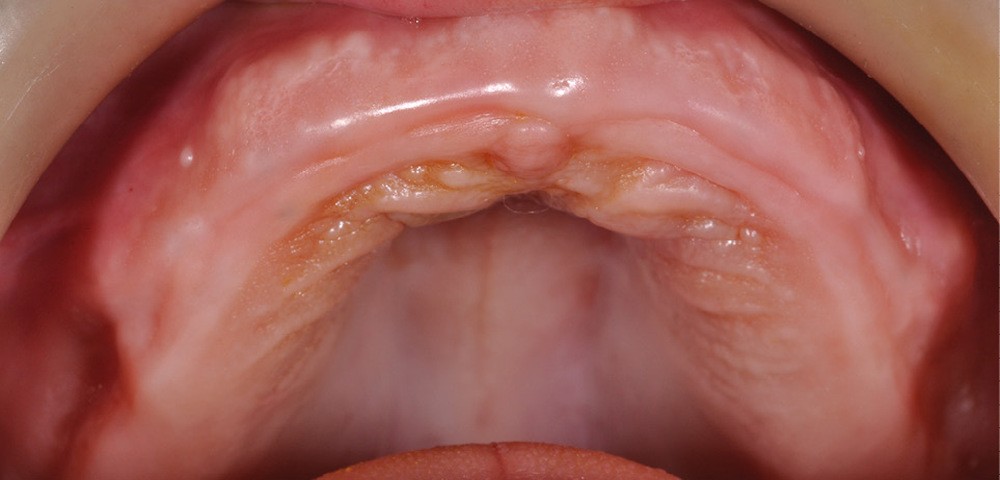

1. Stade préopératoire.

Mais, l’édentation totale s’accompagne fréquemment d’atrophies osseuses, pouvant être accentuées par la sollicitation du port d’une prothèse amovible instable. Au maxillaire, les atrophies anatomiques peuvent alors contre-indiquer la pose implantaire en première intention, principalement en zone postérieure sous sinusale. Aussi, les praticiens sont régulièrement amenés à proposer une étape préliminaire de chirurgie pré-implantaire par greffe d’apposition [7-8], de surélévation sinusale [9-10], de chirurgie orthognatique [11-12]… Si cela correspond à la thérapeutique consensuelle et est la règle à respecter, elle se révèle lourde et compliquée [13].